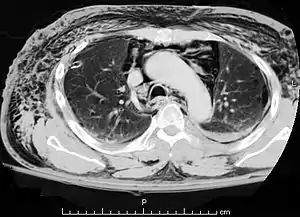

| A CT scan showing air in the mediastinum with subcutaneous emphysema, which can result in Hamman's syndrome | |